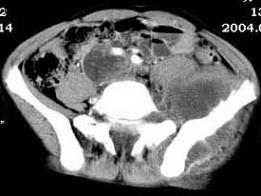

问题 女,35岁,7个月前无诱因出现左下肢阵发性疼痛,左骶髂部活动受限,进行性加重,排便困难,请根据所提供的图像,选择最佳选项 ( )

选项 A、转移瘤 B、滑膜肉瘤 C、软骨肉瘤 D、骨巨细胞瘤 E、脊索瘤

答案 B